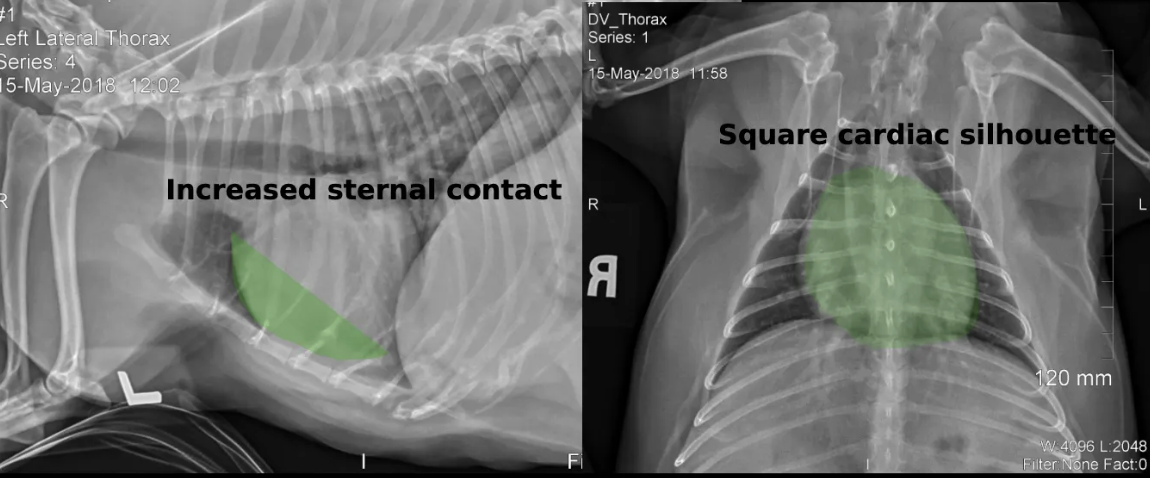

radiographic characteristics of shallow wide chested breeds like french bulldog

A

• blunted cardiac shadow on DV

• more sternal contact mimicking R heart enlargement on lateral